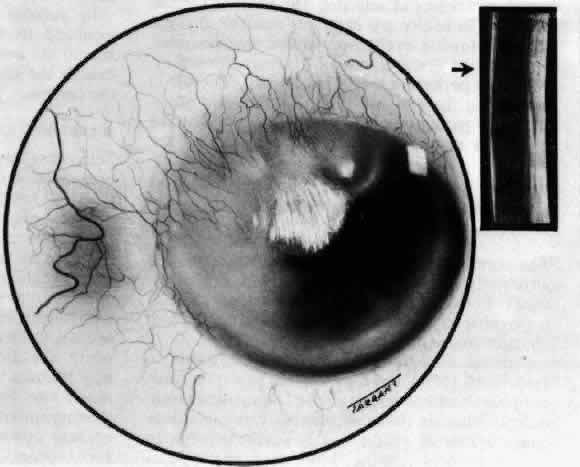

B-scan ultrasonography should never be omitted from the examination of patients with scleritis. Now that high-quality ultrasonography has become available, the extent and severity of the inflammation can be determined with great accuracy. Many patients who were formerly thought to have only anterior segment disease have been found to have extensive and sight-threatening posterior scleritis as well. It also has become known that many patients with posterior scleritis with few symptoms and signs have much more extensive disease than had previously been considered possible (Fig. 9). Anterior segment B-scan ultrasonography sometimes reveals extensive involvement of the deep scleral tissue around the ciliary body, indicating the need for urgent and intensive use of immunosuppressive therapy.

Fig. 9. B-scan ultrasonography in a patient with severe posterior scleritis. Note the thick sclera and the gap between scleral and episcleral tissue posteriorly.

B-scan ultrasonography has proved to be a much more valuable investigation than even high-resolution computed tomography (CT) scanning. However, if orbital extension of disease is thought to have occurred, then CT or magnetic resonance imaging (MRI) should be performed.